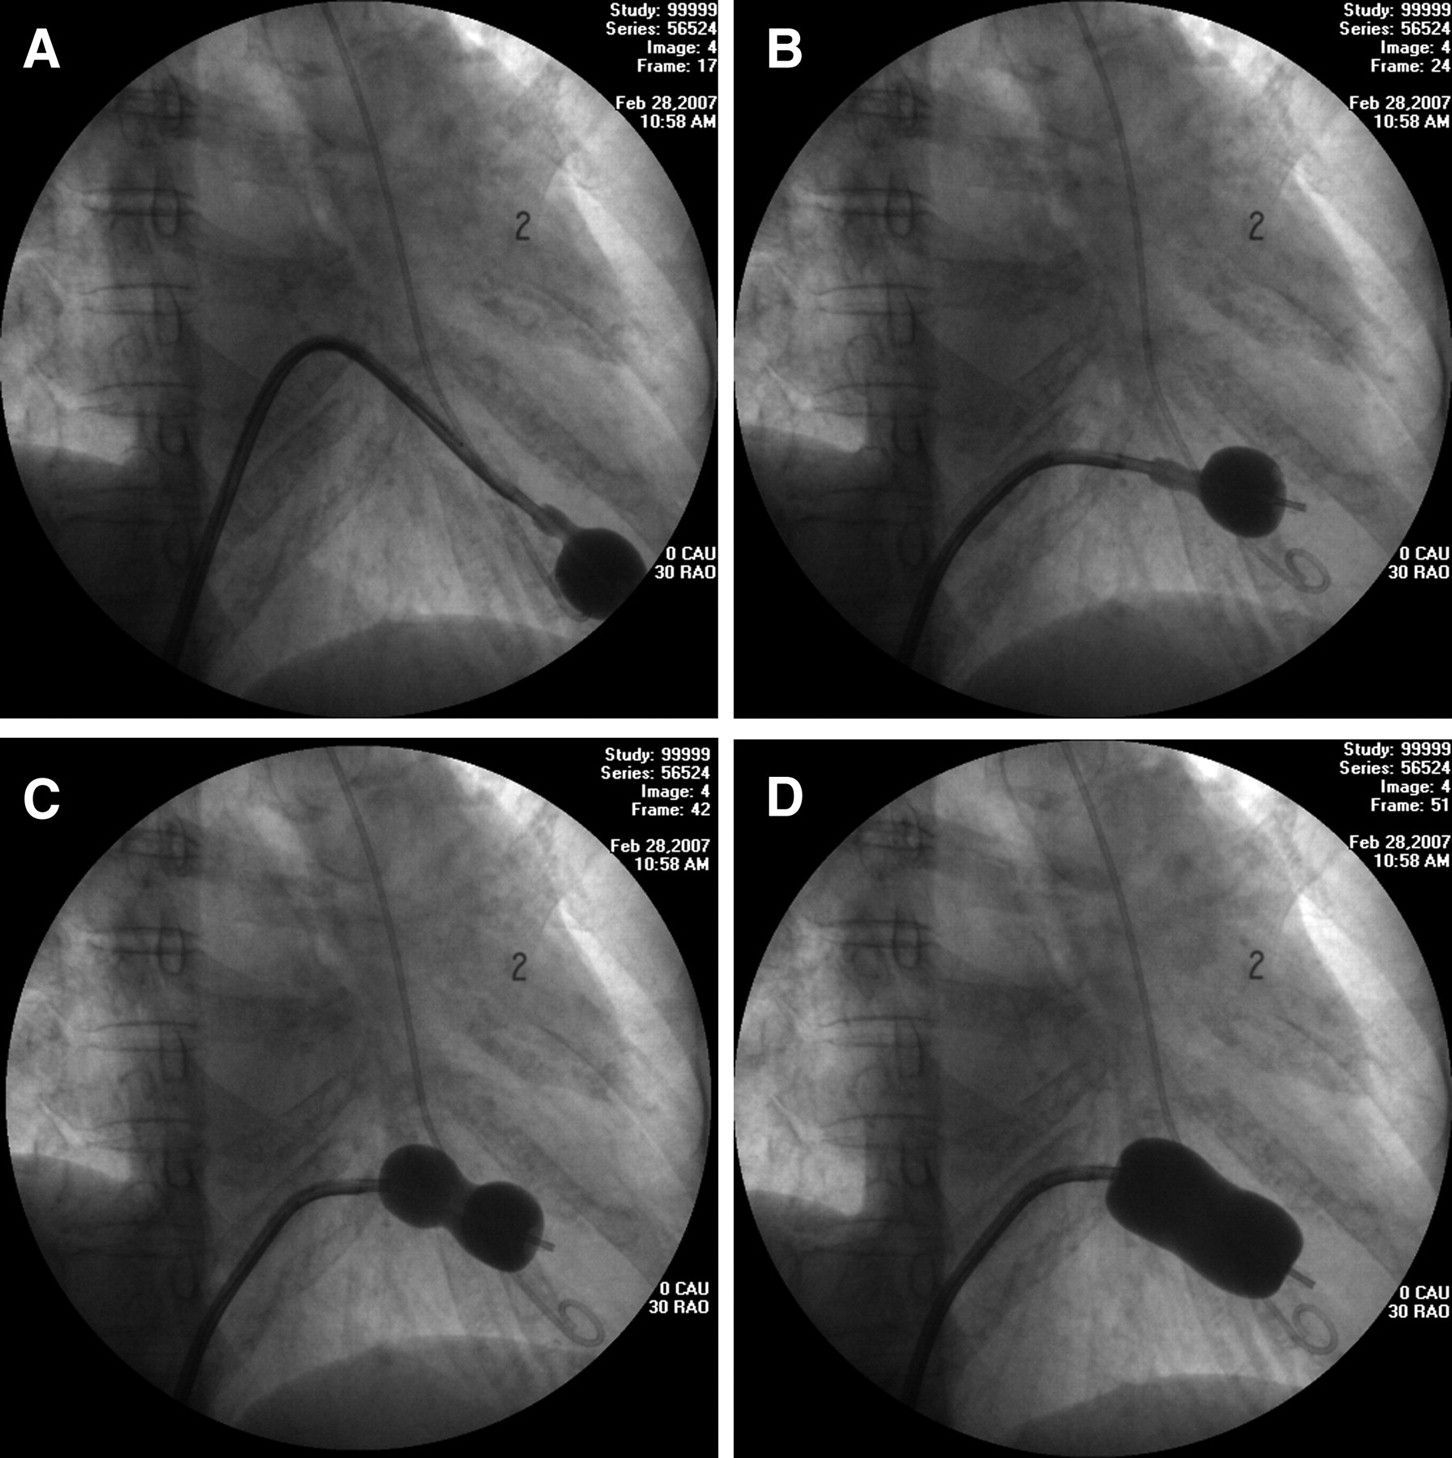

The criteria of mitral balloon valvuloplasty is: - symptomatic mitral valve disease - mitral stenosis - trivial mitral regurgitation - mobile valve - non-calcified valve - mobile, non-calcified subvalvular apparatus - thrombus-free left atrium Reference: Davidson's Principles and Practice of Medicine Image via: https://www.ahajournals.org/doi/full/10.1161/circulationaha.108.792952